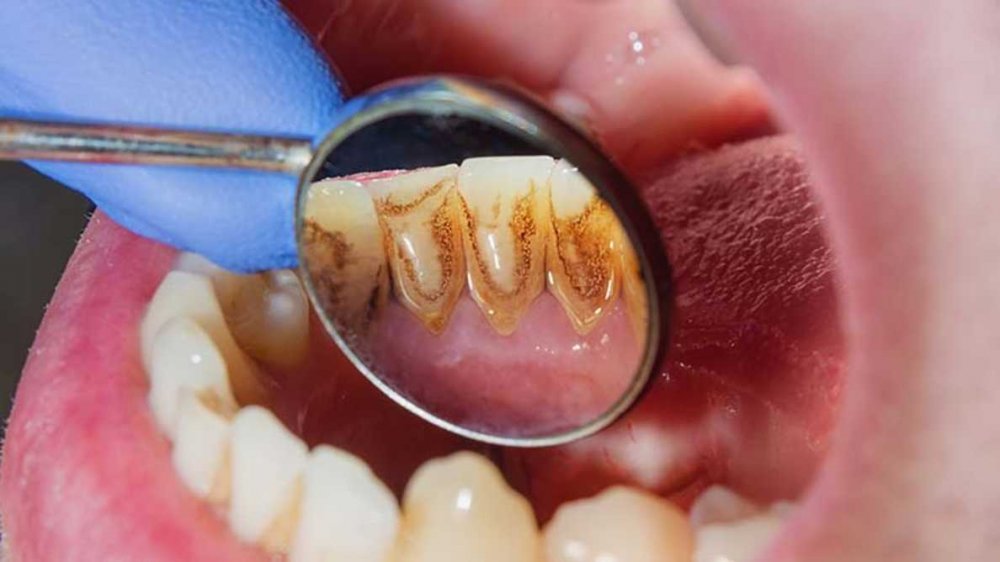

Parodontit, bütünlükdə parodont olaraq bilinən diş köklərini əhatə edən, dəstəkləyən və diş yuvasına fiksə edən xüsusi toxumaların, bağ aparatının və sümüyün iltihabıdır. Parodontit diş əti iltihabının gingivitdən sonrakı ikinci mərhələsi olub, gingivitdən fərqli olaraq müalicə edilmədiyində geri dönməyən degenerativ dəyişikliklərə, diş və onu əhatə edən sümük toxumasının itirilməsinə gətirib çıxara bilir. Parodontitin yaranma səbəbi bakterial plakdır. Lakin xəstəliyin inkişafında bir sıra yerli və ümumi faktorlar da rol oynaya bilir.

- Diş ətində şişkinlik və qızartı

- Diş ətində qanamağa meyllilik